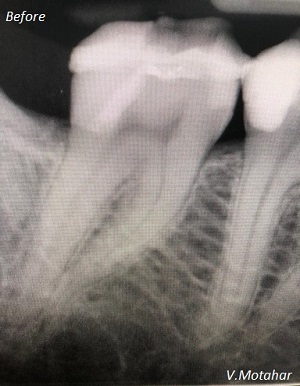

Root Canal Treatment on a molar teeth which had deep decay!

before

after